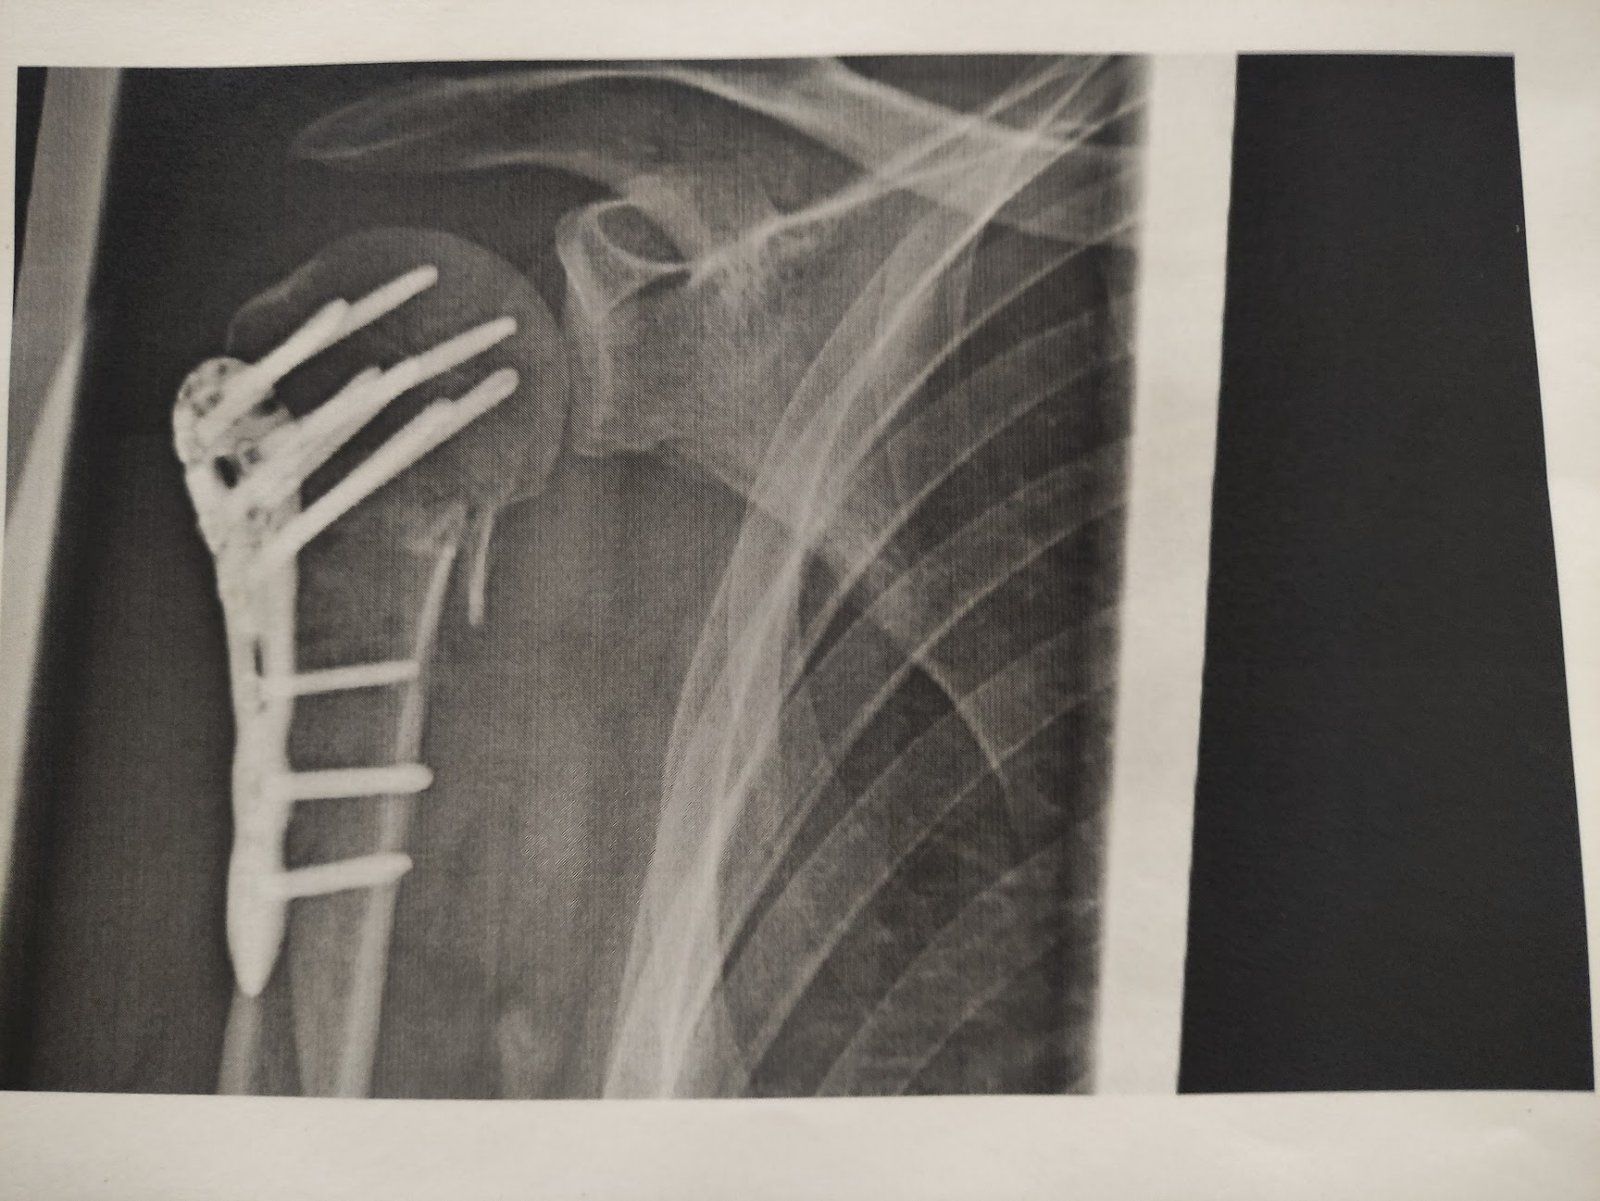

Zwei Wochen danach geht immer noch nichts, ohne Schmerzmittel. Dafür sind die Klammern raus gekommen und es gab Bilder, damit ich endlich auch mal weiß wie es unter der Haut aussieht.

IMG_20210517_173104.jpg